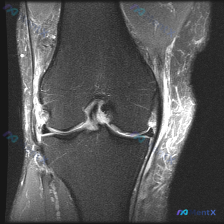

最近看到这份膝关节MRI T2冠状位的病例资料,核心问题是半月板异常,整理了完整的读片思路和大家分享。 病例核心影像信息 本次提供的是膝关节MRI T2序列冠状位图像,核心观察结果如下: 1. 内侧半月板: 体部结构可见,内部没有明显贯穿关节面的高信号,仅边缘形态略不规则 2. 外侧半月板: 体部实...